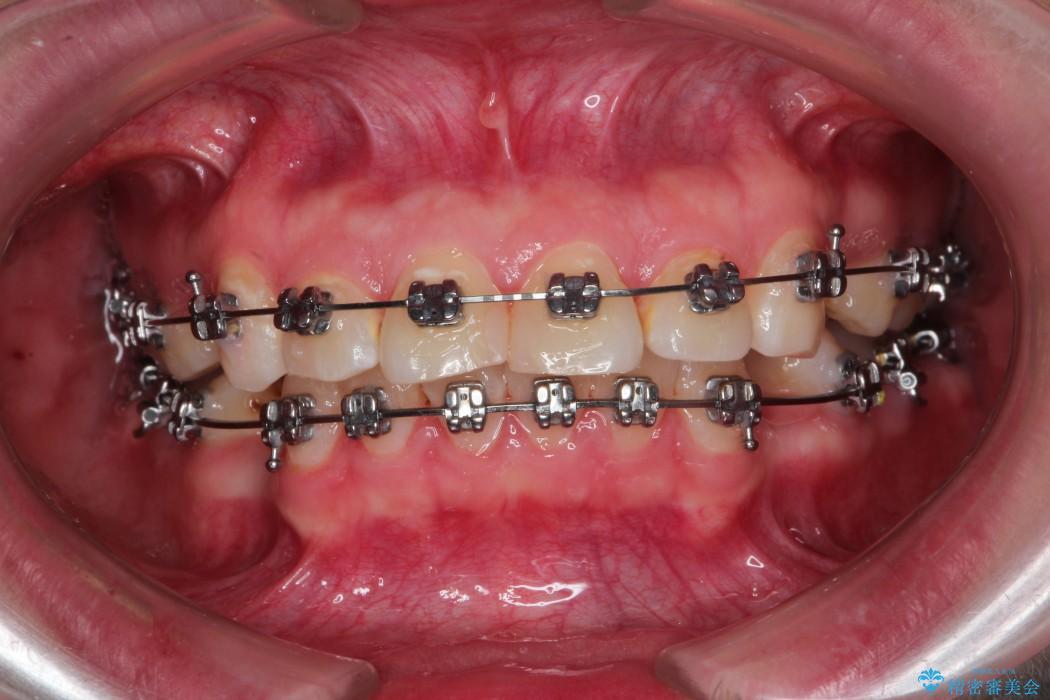

- 矯正装置:メタル装置

治療費の安い矯正治療を希望されていたため、メタルのワイヤー装置にて治療する計画にしました。また、歯みがきが苦手だったため、矯正治療をする前に徹底的にブラッシング指導を行いました。

出ている歯を引っ込めるためのスペースを作るため、上下左右の小臼歯を抜歯し、ワイヤー矯正を行いました。治療後は、口元がスッキリとしたことで患者様にも喜んでいいただきました。